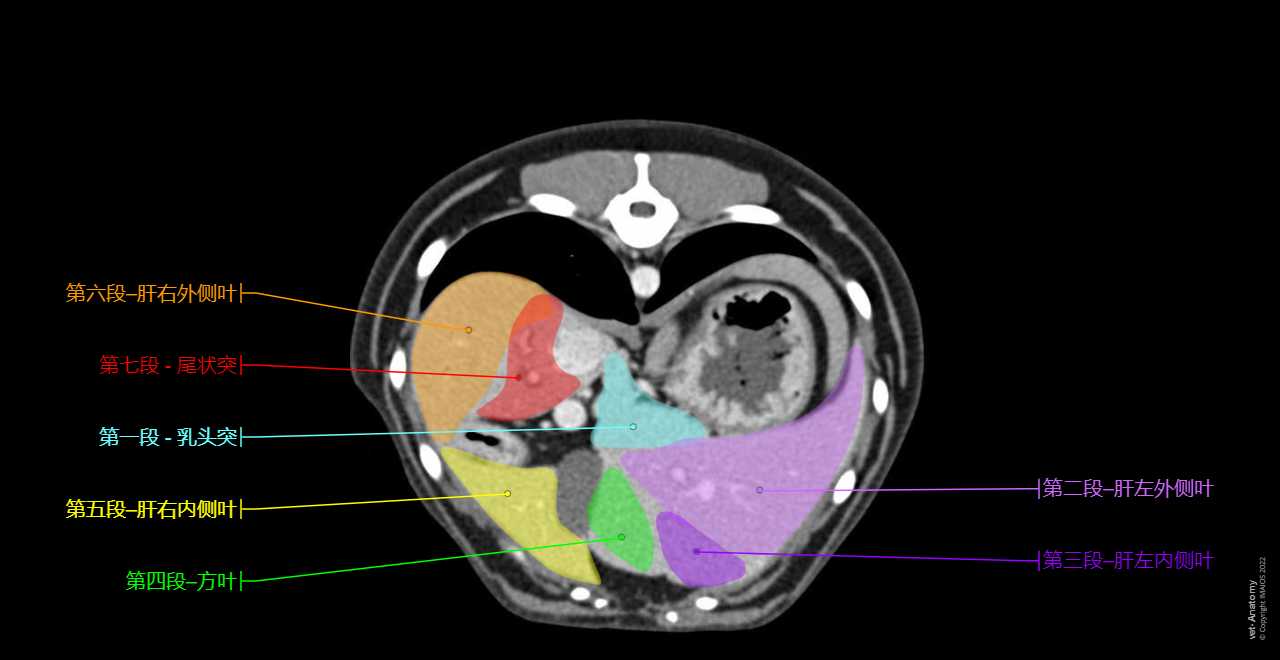

• 该犬在CT上的肝脏分割是Antoine Micheau博士的原创工作:

在犬科动物中,基于解剖学考虑,肝脏分割描述为具有四个叶和四个亚叶以及两个突。这是NAV上使用的术语。

对于某些作者而言,基于人类肝脏八段分段法与犬肝血管解剖结构之间的类比,使用犬肝静脉系统血管解剖可能会减少混淆,因此对该器官的外科手术(以及放射)方法更为有用。

在vet-Anatomy中,我们使用了L. Mari和F. Acocella的发表刊物对犬科动物进行了肝脏分割:犬肝叶和人类肝脏部分看起来具有一定相似性,因此我们采用人类解剖术语进行改编:

部分分区NAV中的常规命名法建议的节段编号建议的命名法人类的对应节段

左外Lobus hepatis sinister lateralis

第二段

第二a段(背侧)

第二b段(腹侧)

第二段-肝左外叶左后侧部分;第二段

左内Lobus hepatis sinister medialis第三段第三段-肝左内叶左前侧部分;第三段

中央方形Lobus quadratus第四段第四段-肝方叶左内侧部分;第四段

右内侧Lobus hepatis dexter medialis第五段第五段-肝右内叶前内侧部分;五区

尾状叶乳突Processus papillaris第一段第一段-乳头状突后段;尾状叶;第一段

右外Lobus hepatis dexter lateralis

第六段

第六a段(背侧)

第六b段(腹侧)

第二段-肝右外叶前侧节段;第六段

尾状叶尾状突Processus caudatus第七段第七段-尾状突后外侧部分;第七段

狗没有第八段后内侧部分;第八段

有关肝脏分割的注释:

• 在NAV中,尾突和乳突包含在同一个叶中——即尾状叶。但是由于这两个突在左右血管形成方面有所不同,因此不能在此肝脏分割中的同一叶中,这与人类肝脏分割相反,在人类肝脏分割中,尾状叶是第一部分,并且包含尾突和乳突。

• 该犬中没有第八部分。

Hepatic segmentation - Dog - CT